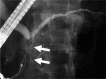

IgG4-related sclerosing cholangitis (IgG4-SC) is a distinct type of cholangitis frequently associated with autoimmune pancreatitis and currently recognized as a biliary manifestation of IgG4-related disease. Although clinical diagnostic criteria of IgG4-SC were established in 2012, differential diagnosis from primary sclerosing cholangitis and cholangiocarcinoma is sometimes difficult. Furthermore, no practical guidelines for IgG4-SC are available. Because the evidence level of most articles retrieved through searching the PubMed, Cochrane Library, and Igaku Chuo Zasshi databases was below C based on the systematic review evaluation system of clinical practice guidelines MINDS 2014, we developed consensus guidelines using the modified Delphi approach. Three committees (a guideline creating committee, an expert panelist committee for rating statements according to the modified Delphi method, and an evaluating committee) were organized. Eighteen clinical questions (CQs) with clinical statements were developed regarding diagnosis (14 CQs) and treatment (4 CQs). Recommendation levels for clinical statements were set using the modified Delphi approach. The guidelines explain methods for accurate diagnosis, and safe and appropriate treatment of IgG4-SC.